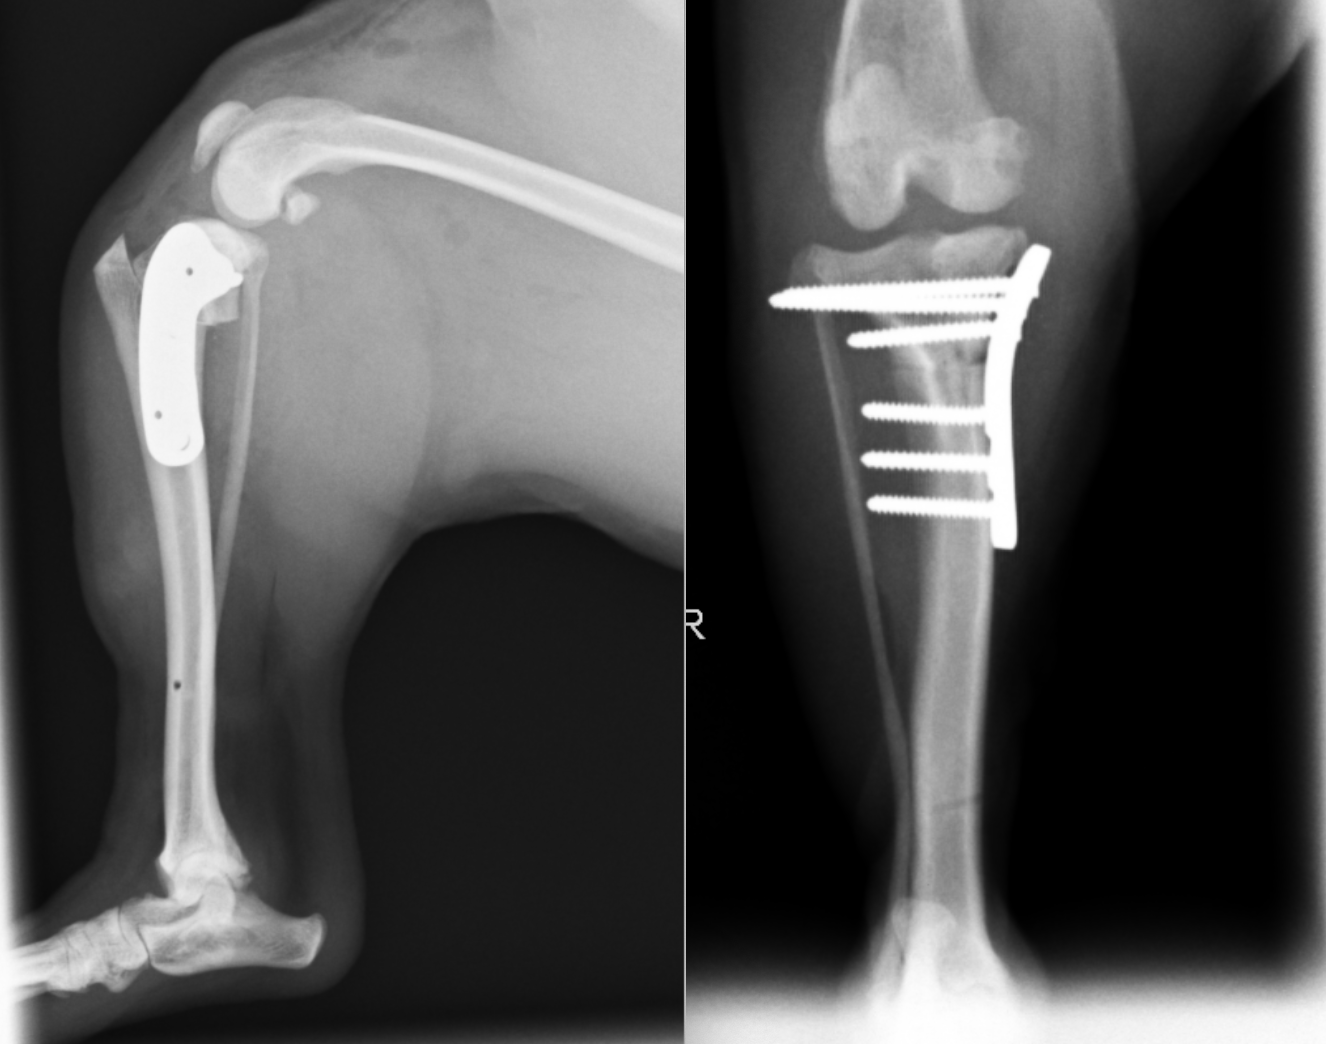

術後のレントゲン画像です。先程までずれていた矢印が合っているのがわかります。

またTPAと呼ばれる角度も小さくなっているのが確認できます(6°)。6°前後が理想的と言われています。

35kgの黒ラブラドールです。術後TPAは7°と、理想的な角度となっています。この症例もすぐに歩きだし、跛行もなくなりました。